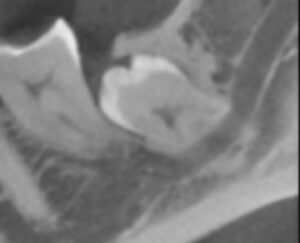

Weisheitszahn begünstigt die Kariesbildung an Nachbarzähnen – Auf dem ersten Bild ist ein Weisheitszahn (schwarzer Pfeil) abgebildet. Dieser ist nur teilweise durch die Schleimhaut durchgebrochen und erschwert die Zahnreinigung am Nachbarzahn. In der Folge hat sich an diesem Zahn eine große Karies gebildet. Die Karies ist zum besseren Verständnis auf dem zweiten Bild durch eine rote Umrandung hervorgehoben. Es ist deshalb ratsam Weisheitszähne, die die Zahnreinigung erschweren, rechtzeitig zu entfernen.